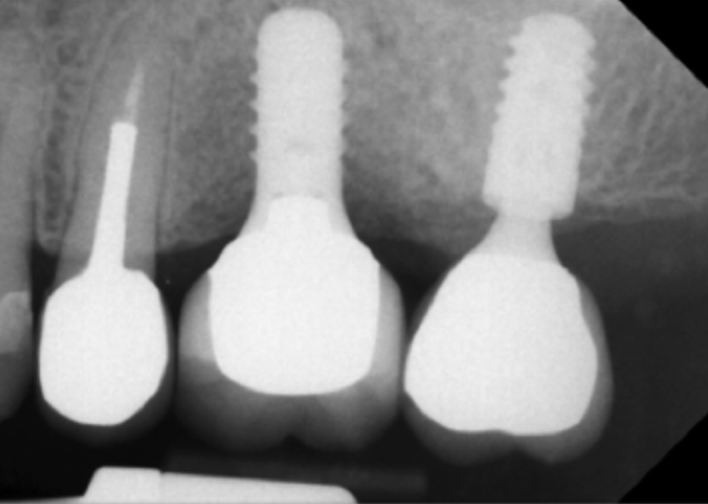

To avoid potential soft tissue collapse when the impression was captured, a custom impression abutment was created to support the soft tissue and properly communicate to the laboratory technician what had developed intraorally (Figure 10). This technique may be used with either open-tray or closed-tray impression abutments. The impression was taken and the custom healing abutment was reinserted intraorally while the laboratory constructed the restoration. The completed restoration was returned, the custom healing abutment was removed, and the implant restoration was inserted. The result was an emergence profile that mimicked a natural molar, enabling natural-looking esthetics (Figure 11). A radiograph demonstrated a smooth transition emanating from the implant platform to support an emergence profile that allowed soft-tissue maintenance and helped to eliminate potential food traps (Figure 12).

Fig 12. Radiograph of the final restoration demonstrating a natural emergence profile of the tooth that was replaced.

Figure 12